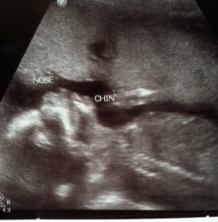

We are very excited to welcome a new little one later this year.  Arrival is expected in early June and so far everything is going well, which is such a blessing.  This is the reason I am currently not training for any particular races.  I'm working to keep moving as much as possible, which worked out well for me with our first bundle.  My first trimester was a challenge between some busy schedules, a work trip for my husband and not feeling so well.  I seem to have more energy during the second trimester though and I am getting a decent workout in 4-5 days per week, preferably 5!